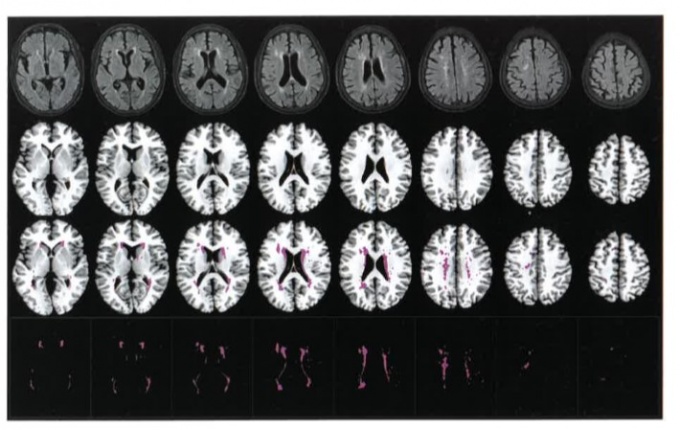

¿©±â¿¡´Â µ¥ÀÌÅÍÀÇ Á¤·®±¸ÃàÀ» À§ÇØ ¼¾ÅͰ¡ °³¹ßÇÑ ¼ÒÇÁÆ®¿þ¾î ‘Image_Q NA’°¡ »ç¿ëµÆ´Ù. Image_Q NA´Â ³úÁ¹Áß¿¡ °ü·ÃµÈ ³úº´º¯À» ÁÂÇ¥ °ø°£ À§¿¡ ºÐÇÒÇÑ´Ù. ¾Æ³¯·Î±× ¹æ½Ä¿¡¼­ ‘¿ÞÂÊ ¾îµðÂë’À̶ó°í ºÒ·¯¾ß Çß´ø º´º¯Àº ÀÌ °úÁ¤¿¡¼­ xÃà°ú yÃàÀÇ ÁÂÇ¥ °ªÀ» °¡Áø´Ù. ³ú ¼Ó º´º¯ À§Ä¡¿Í Å©±â µîÀÌ ºÐ¼® °¡´ÉÇÑ ¼öÄ¡·Î º¯È¯µÇ´Â ¼ÀÀÌ´Ù.

BMP ÅÛÇø´À» ÀÌ¿ëÇÑ ³úÇãÇ÷ º´º¯ µî·Ï ¿¹